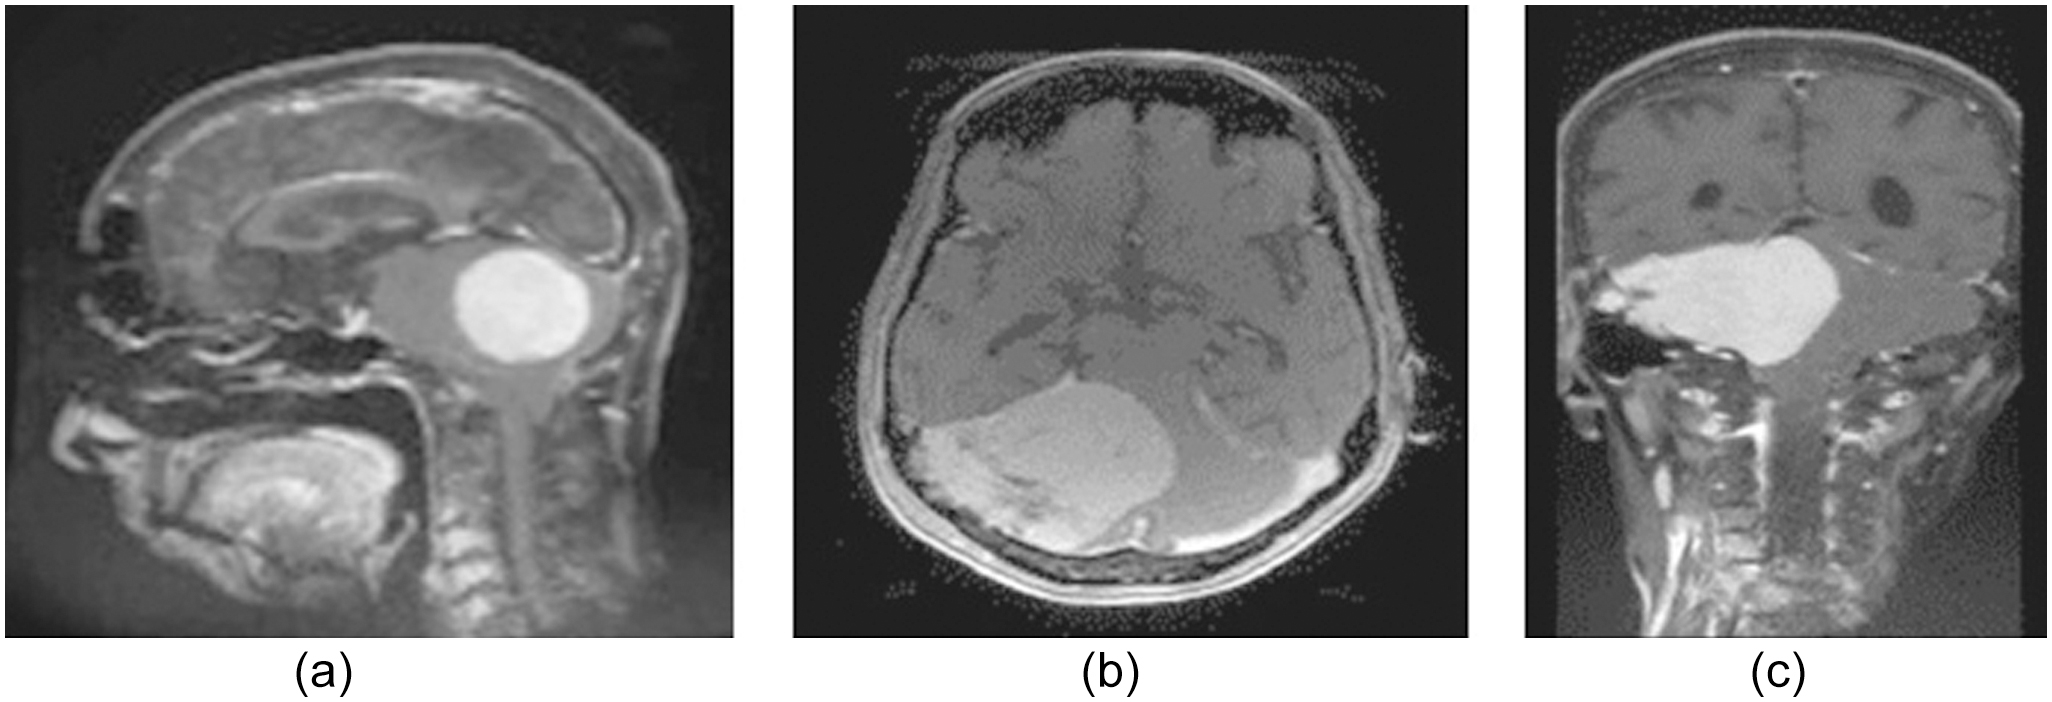

Medical practitioners can examine the morphology of tumors in three dimensions (sagittal, axial, and coronal) using the MRI images, as illustrated in Fig. 5.

Fig. 5. (a) Sagittal, (b) axial, besides and (c) coronal plane.